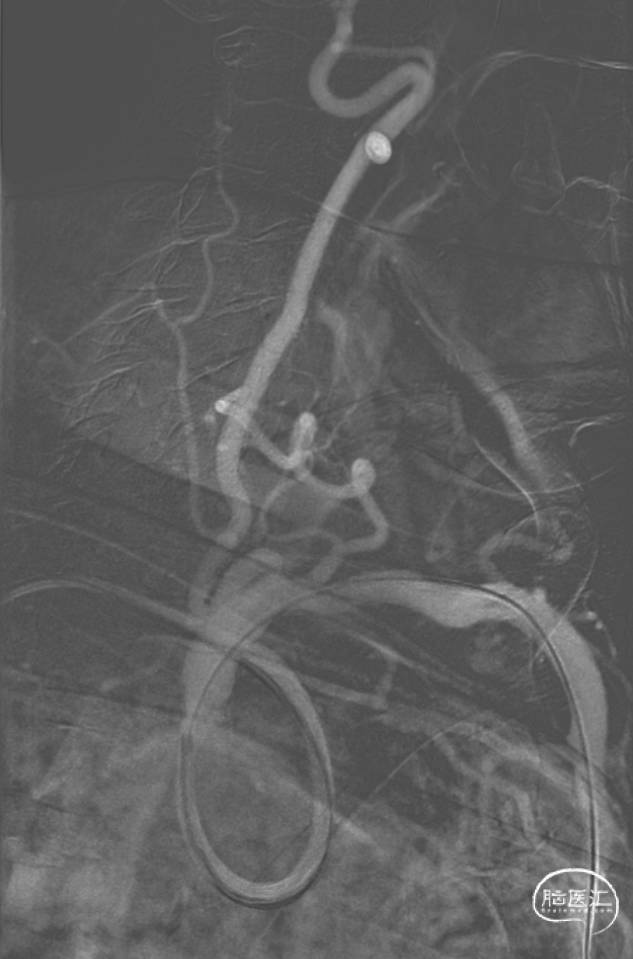

导引导管到位:

使用Simmons 2导管送达左侧锁骨下动脉,长泥鳅导丝超选左侧腋下动脉,交换撤出Simmons 2导管,送入SPB 3.5导引导管至左侧锁骨下动脉起始部。

微导丝到位:

在路图指引下将微导丝谨慎通过狭窄及V1迂曲段并留置于左侧椎动脉V3段远段。

操作要点:

1、微导丝塑形,使用双导丝技术

2、微导丝操控,谨慎通过狭窄段

5

经过测量后,选择4.0mm*13mm Bridge椎动脉雷帕霉素靶向洗脱支架,沿微导丝将支架输送至狭窄处,造影确认位置良好,缓慢充盈至10atm,30s后泄压,造影见支架定位良好,残余狭窄约为40%,再次送入球囊扩张,10atm缓慢充盈,30s后泄压,造影见支架定位良好,贴壁良好,前向血流较前改善,无残余狭窄。